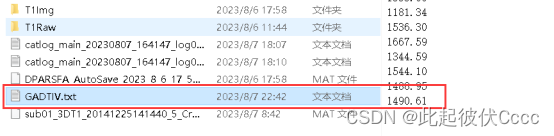

在与T1Raw相同文件夹的T1Img文件中生成了图像格式转换后的.nii文件,如下图所示:

其中sub01_3DT1_20141225141440_5_Crop_1.nii文件便是我们后期需要处理的.nii文件,用mricron软件查看图像如下图所示: